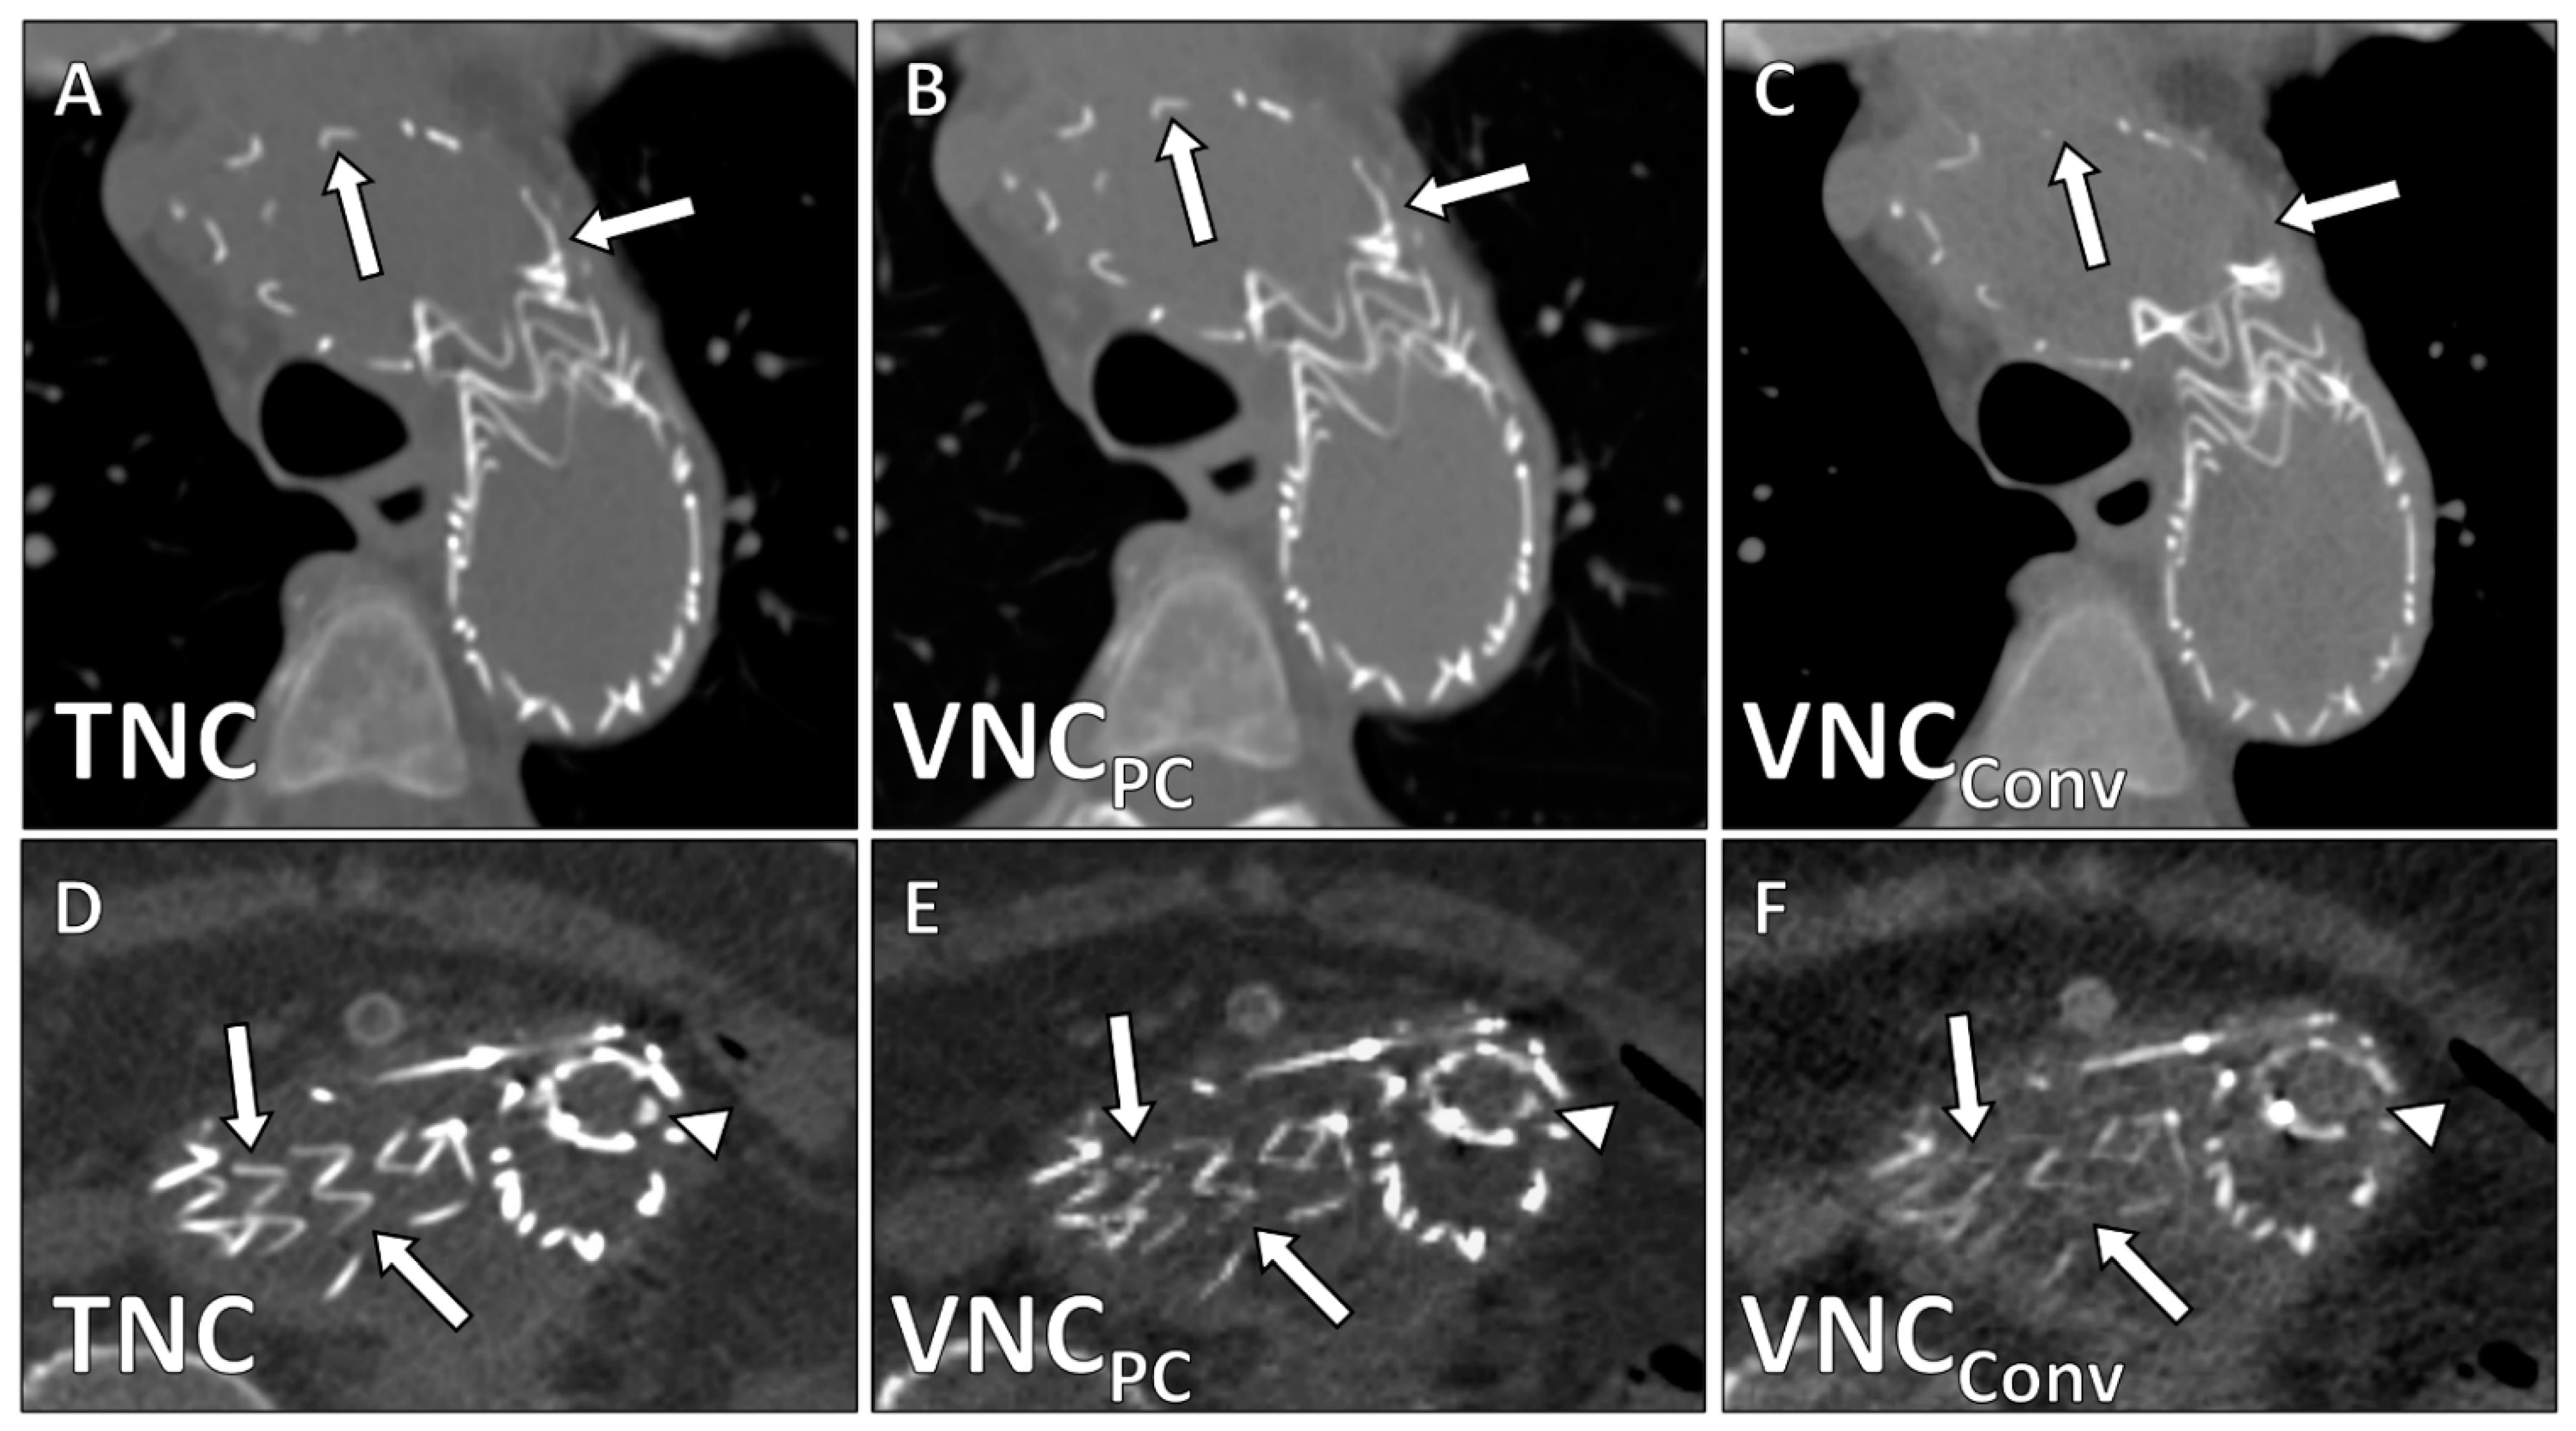

| Image Quality | 4.2 ± 0.9 | 0.68 (0.44–0.78) | 2.5 ± 0.6 | 0.62 (0.43–0.77) | <0.001 |

| Calcium Subtraction | 4.6 ± 0.5 | 0.75 (0.66–0.82) | 3.0 ± 0.6 | 0.58 (0.40–0.71) | <0.001 |

| Stent Subtraction | 4.7 ± 0.7 | 0.72 (0.58–0.81) | 3.8 ± 1.2 | 0.62 (0.49–0.77) | 0.003 |